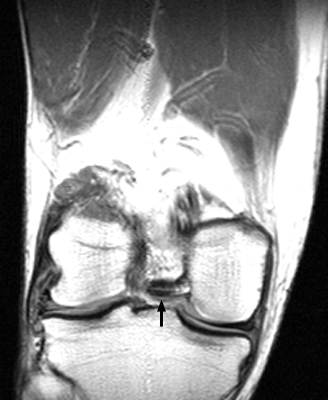

Fragment-in-Notch Sign

Bucket-handle tear of the menisci

The displaced fragment of a bucket handle tear of the meniscus can move medially to lie within the intercondylar notch. The fragment-in-notch sign is defined as a band like area of low signal intensity within the intercondylar notch, not appearing on the same slice as the PCL. The sign, when identified, can be valuable in picking up a bucket handle tear of the meniscus.